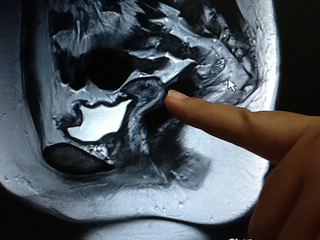

27歲的她 子宮小如水餃--- 聯合報報導博元婦產科:蔡鋒博說,也...

27歲的她 子宮小如水餃--- 聯合報報導博元婦產科:博元婦產科醫...